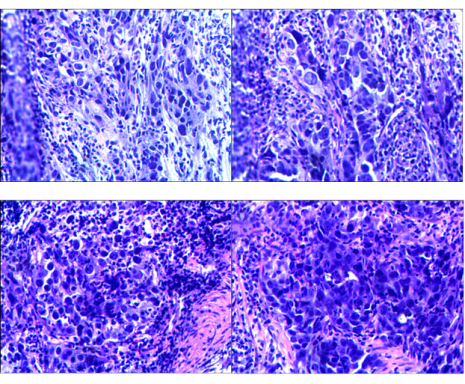

图2 胃镜活检组织病理切片

肿瘤分子病理: